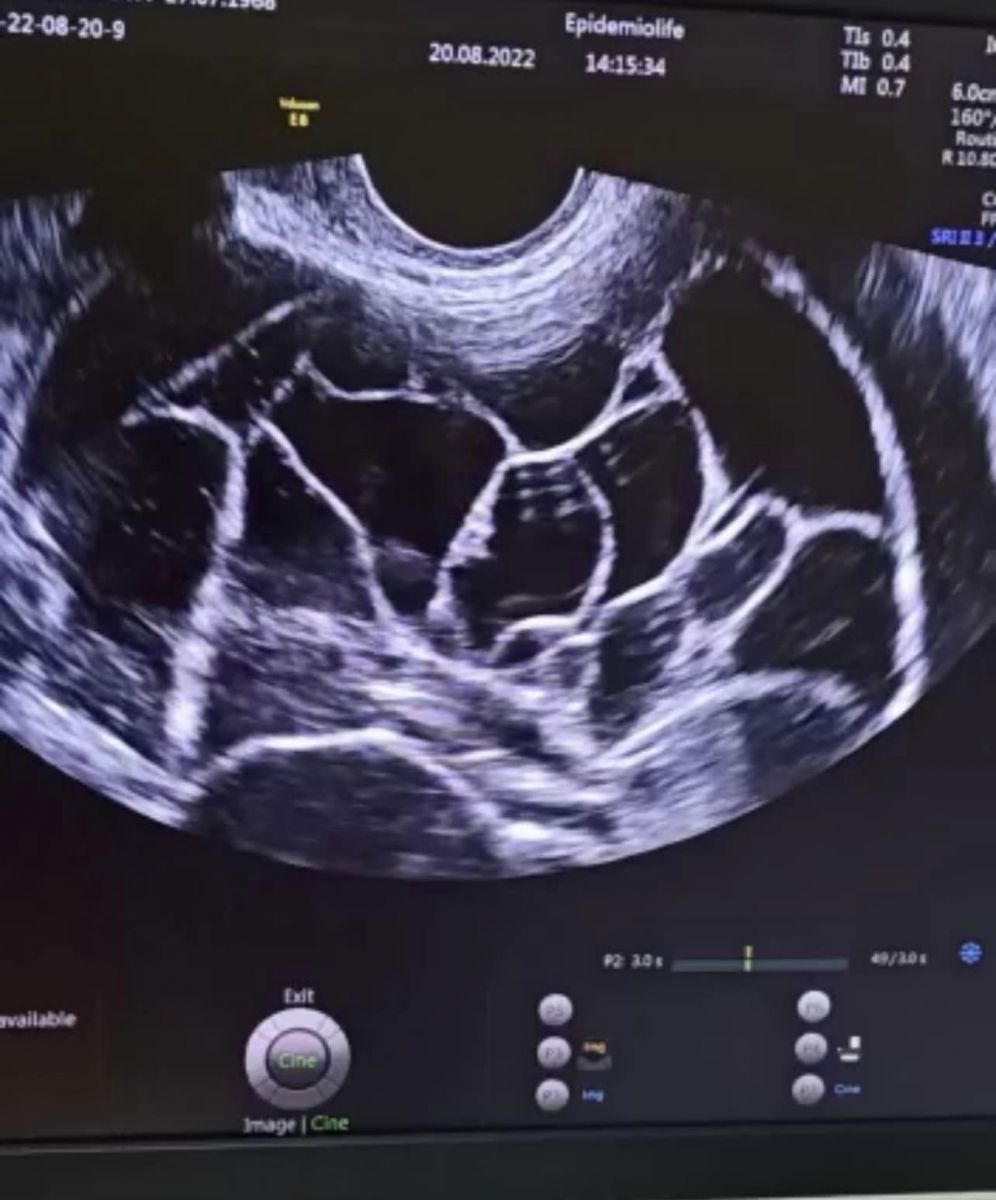

”Ecografic am depistat o formațiune chistica cu multe septuri la nivelul ovarului drept, de aproximativ 20 cm, cu prezență de lichid liber în burtă și o altă formațiune cu caracter solid și vascularizație intensă localizată subcutanat la nivel suprapubian, de aproximativ 7 cm”,

Dr. Alexandra Ciobanu